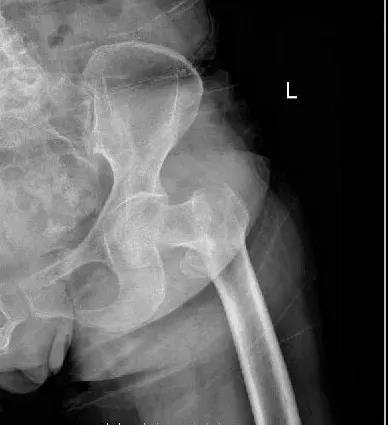

濰坊市濰城區(qū)的高大娘6年前行腦瘤手術(shù),術(shù)后反復(fù)癲癇發(fā)作,遺留了左側(cè)肢體活動不靈活的后遺癥,并且有房顫病史5年,近日凌晨起床去廁所時不慎摔倒,當(dāng)即感到左髖部疼痛明顯,不能站立及行走,在家休息后未見明顯好轉(zhuǎn),家人遂將高大娘送到我院做診治,經(jīng)過骨科副主任孫守全查體考慮為老年人常見的髖部骨折,遂給于髖部拍片檢查示:左側(cè)股骨粗隆間粉碎性骨折。

考慮這類骨折的特點,孫主任為高大娘及家屬進行了詳細的解釋,并建議收住院行手術(shù)治療,高大娘住到了我院的骨科病房,在孫主任帶領(lǐng)下骨科醫(yī)務(wù)人員為高大娘做了詳細的病情討論。因為高大娘往有腦瘤手術(shù)史,癲癇、高血壓病、心房纖顫等內(nèi)科基礎(chǔ)病史,院外服用多種藥物治療,平素左側(cè)肢體活動不靈活,考慮病人的個體因素及年齡,決定為步大娘做PFNA內(nèi)固定術(shù),減少手術(shù)時間,縮短臥床時間,盡早下地活動,提高生活質(zhì)量。在麻醉科、心內(nèi)科多學(xué)科的協(xié)助下,經(jīng)過周密的術(shù)前準(zhǔn)備,排除明顯手術(shù)禁忌,我院骨科團隊為高大娘順利完成左股骨粗隆間粉碎性骨折閉合復(fù)位PFNA內(nèi)固定術(shù),病人術(shù)后3天就可以在保護下下地活動了,病人的快速康復(fù)不僅給病人帶來了生活的信心,也大大解決了家人護理的麻煩,高大娘及家屬對我院骨科的治療方案及治療結(jié)果非常滿意。